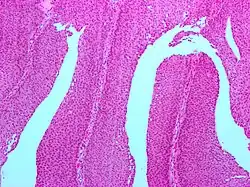

Micrograph of a PUNLMP. Intermediate magnification. H&E stain. | |

Papillary urothelial neoplasm of low malignant potential (PUNLMP) is an exophytic (outward growing), (microscopically) nipple-shaped (or papillary) pre-malignant growth of the lining of the upper genitourinary tract (the urothelium), which includes the renal pelvis, ureters, urinary bladder and part of the urethra.

Histologically, they have a papillary architecture with slender fibro vascular cores and rare basal mitoses. The papillae rarely fuse and uncommonly branch. Cytologically, they have uniform nuclear enlargement.